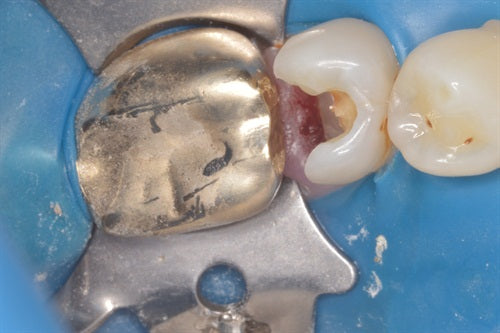

#16 Large composite by Dr. Ahmad Fayad

Posted on February 24 2018

The below case was completed and documented by our guest presenter, Dr. Ahmad Fayad. This is a great example of a Greater Curve band and technique at work! Introduction: In... Read More